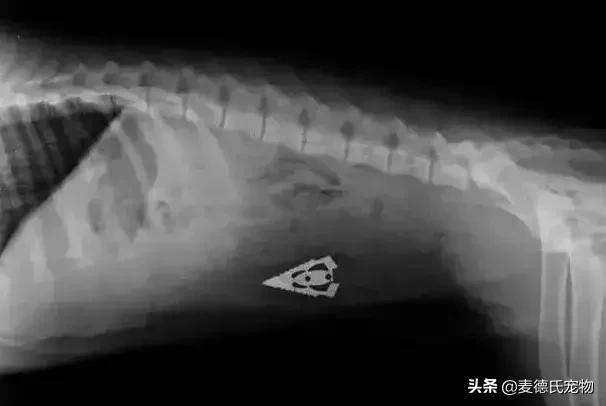

不明三角...